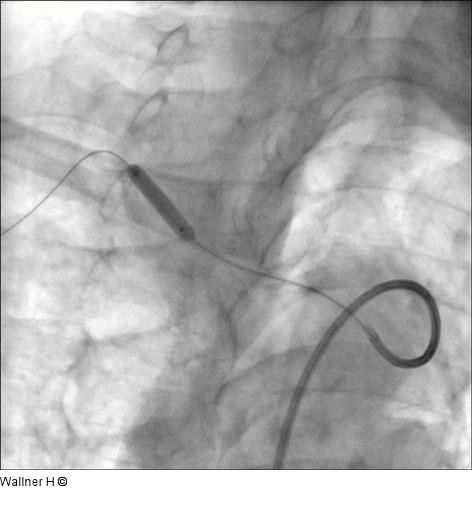

Abbildung 4: Stentposition Freisetzung des selbstexpandierenden Stents (Luminexx 3™, 14x30/135cm, Bard. Technisch war es notwendig, den Draht zurückzuziehen, um eine optimale Stentposition zu erreichen. |

Freisetzung des selbstexpandierenden Stents (Luminexx 3™, 14x30/135cm, Bard. Technisch war es notwendig, den Draht zurückzuziehen, um eine optimale Stentposition zu erreichen. |